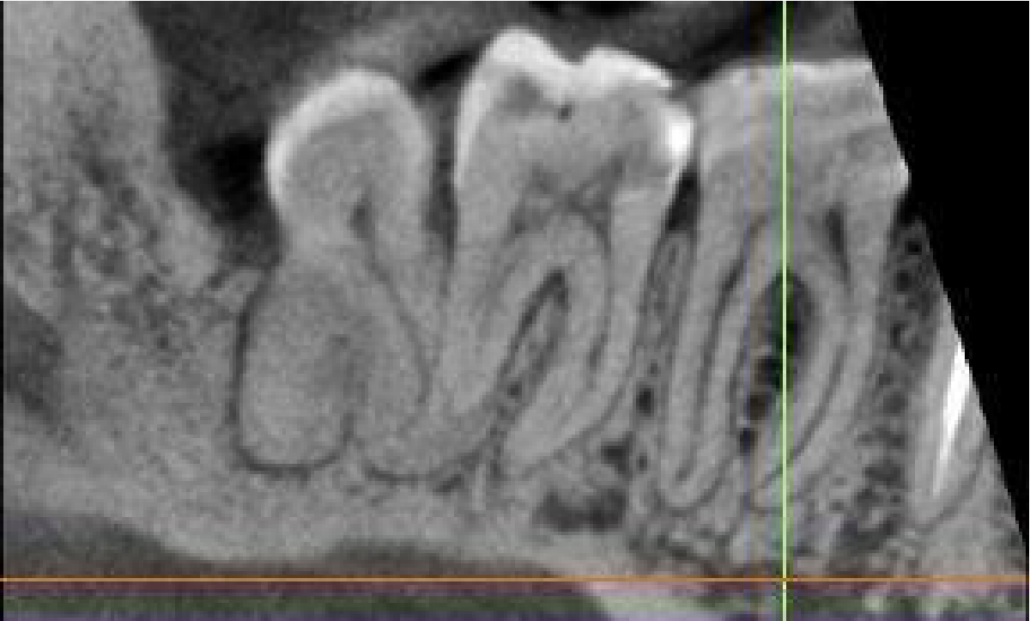

Cropped panoramic of LR6-8 and cross section of alveolar ridge of LR6 region showing patent root canals, normal periodontal ligament width and lamina dura. Also seen is the enlarged follicle space associated with the LR8.

Cropped panoramic of LR6-8 showing pulp stones in the LR6, LR7 and LR8.